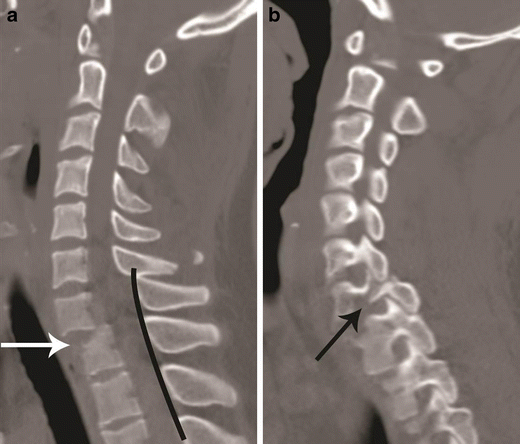

Flexion teardrop fracture. Sagittal CT image of cervical spine in a young patient following vehicular accident shows wedging of C5 vertebral body with an oblique coronal fracture of the anterior third of the vertebral body, dividing the C5 in to a smaller anterior triangular fragment (short arrow) and a large posterior segment. Retrolisthesis of the C5 vertebral body on C6 behind the fracture line and retropulsed C5 keeping alignment with the cranial C4 vertebral body—suggested by non-interrupted posterior vertebral line (black line), while triangular fragment keeping alignment with the caudal C6 vertebra—suggested by non-interrupted anterior spinal line (white line). Distraction of posterior column is suggested by widening of interspinous/interlaminar space at C4–C5 (long arrow). Facet joint subluxation was seen on the parasagittal images (not shown)

Bilateral versus unilateral facet joint dislocation. a Mid-sagittal CT image shows anterior translation of C5 over C6 by more than 50 % anteroposterior width of the C6, highly suggestive of bilateral facet joint dislocation, which was confirmed on parasagittal images (not shown). Large triangular bony fragment is noted at the posteroinferior corner of C5 (arrow) with diffuse loss of C5–C6 intervertebral disc space. b Mid sagittal CT image shows anterior translation of C4 over C5 by less than 50 % anteroposterior width of C5 (approximately 25 %), highly suggestive of unilateral facet joint dislocation, which was confirmed on parasagittal images (not shown). Small triangular bony fragment is noted at the anteroinferior corner of C4 (arrow) with loss of C4–C5 disc space. Disruption of spinolaminar line (black curved lines) at the level of anterolisthesis with anterior displacement of the same vertebra and lamina (C5 in a and C4 in b) is highly suggestive of hyperflexion injury. Presence of small avulsion fragments at the discovertebral junction with loss of intervertebral disc height is associated with disc injury, which needs further evaluation with MRI